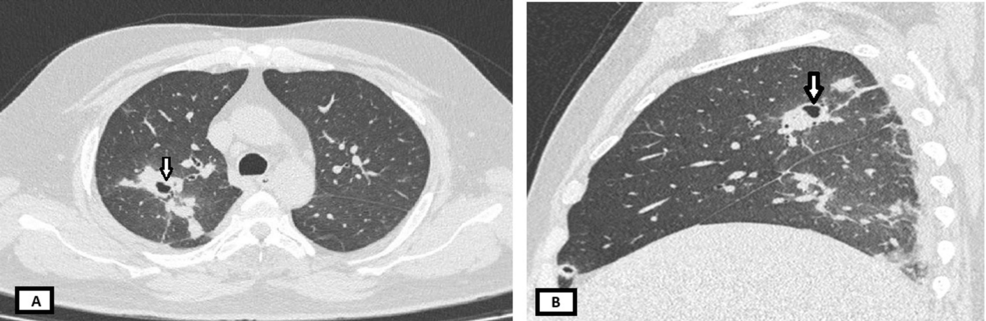

• Pulmonary Melioidosis Masquerading As Tuberculosis: A Case Report Presenting a Rare Medical Condition From Western India

Pulmonary Melioidosis Masquerading As Tuberculosis: A Case Report Presenting a Rare Medical Condition From Western India